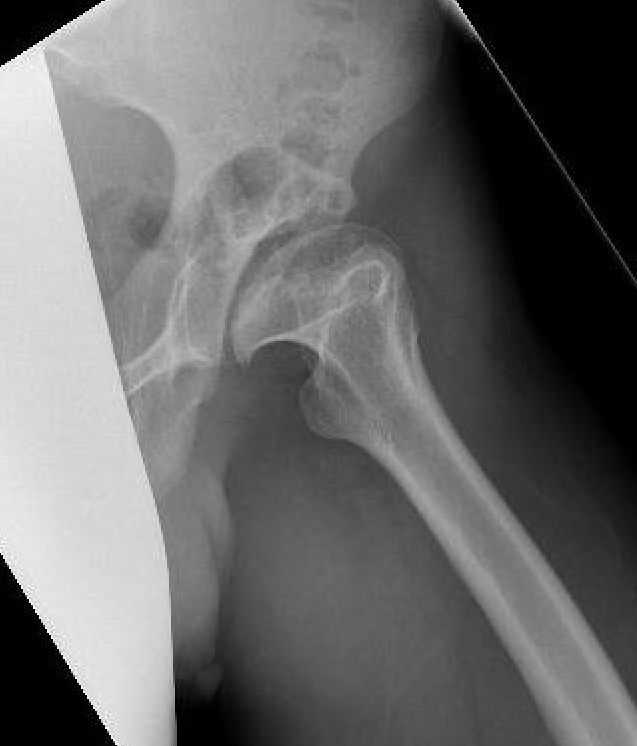

Hanna et al Arch Orthop Trauma Surg 2017

- 6 studies and 245 THA in Perthes

- intra-operative fracture 11% reduced with used of modular stems

- sciatic nerve palsy 3% associated LLD 1.9 cm and previous surgery

- 99 THA for Perthes

- follow up 8 +/- 5 years

- 10% revision rate

- 9% intraoperative fracture (mostly femur)

- 3 sciatic nerve injury with lengthening of 2.2 +/- 1 cm